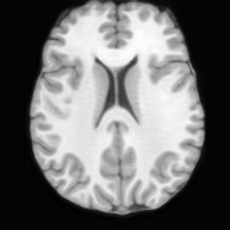

(a)PathologicalInput ImageSynthSR [18]Brain-ID [28]UNA [30]USBHealthyGround TruthRefer to captionRefer to captionRefer to captionRefer to captionRefer to captionRefer to captionRefer to captionRefer to captionRefer to captionRefer to captionRefer to captionRefer to captionRefer to captionRefer to captionRefer to captionRefer to captionRefer to captionRefer to captionRefer to captionRefer to captionRefer to captionRefer to captionRefer to captionRefer to caption(b)HealthyInput ImageConditionalLesion MaskUNA [30]USBRefer to captionRefer to captionRefer to captionRefer to captionRefer to captionRefer to captionRefer to captionRefer to captionRefer to captionRefer to captionRefer to captionRefer to captionRefer to captionRefer to captionRefer to captionRefer to caption

Figure 5: Comparison of bidirectional brain editing. (a) pathology-to-healthy, the circles and arrows highlight lesion regions and unsuccessful reconstructions; (b) healthy-to-pathology. Note that SynthSR and Brain-ID cannot perform healthy-to-pathology editing.

Pathology-to-Healthy Editing. Fig. 5 (a) presents comparison results on four input brain images with lesions of varying sizes, shapes, and densities. All competing models, although specialized for healthy brain image synthesis, struggle to reconstruct pathological regions, especially near lesion boundaries. In contrast, USB accurately reconstructs the corresponding healthy brain, even in challenging cases with large, high-density lesions where normal brain structures are almost completely obscured (last row). Tab. 2 provides a quantitative comparison for pathology-to-healthy editing, where USB achieves the best performance across all three datasets, demonstrating the effectiveness of its unified framework in reconstructing healthy brains from pathological inputs. Additional results are in Suppl. B.